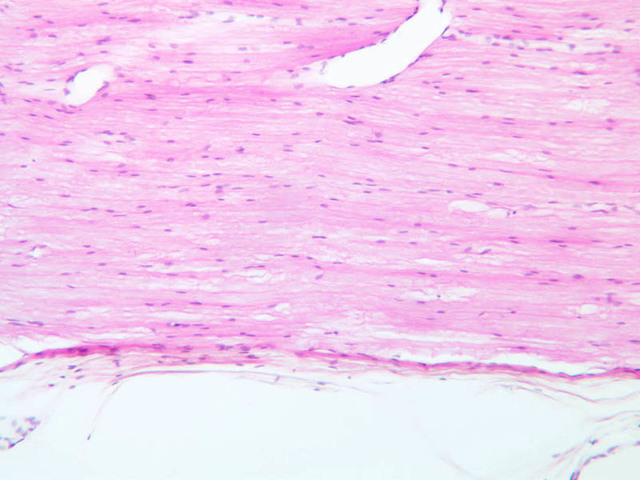

In slide A-82 of spinal cord, find the white matter (A-82, H&E [10x, 20x, 40x] [20x, 40x-labeled]), which surrounds the gray matter ([2.5x, 10x, 20x, 40x]). Does its appearance remind you of a peripheral nerve in cross section? The white matter is comprised of axons that originate from neuronal cell bodies lying in the gray matter of either spinal cord, brain, or spinal ganglia. Axons in the white matter can be thought of as parallel cables that ascend or descend the length of the spinal cord. The white matter does not contain any neuronal cell bodies, thus the nuclei present in this area are those of oligodendroglia, fibrous astrocytes, microglia, or endothelial cells. These cells become readily distinguishable with immunohistochemistry.

On slide A-88 (H&E of spinal cord cut longitudinally [2.5x, 10x, 20x, 40x-labeled] [10x, 20x, 40x-labeled]) look in the white matter at the edges of the section for small cells with darkly stained, round nuclei. These will be oligodendrocytes. In particular look for rows of adjacent oligodendrocytes. Also situated among the nerve fibers in the white matter are fibrous astrocytes. These are easier to find in the white matter of the spinal cord in cross section (slide A-82). Astrocytes have star-like morphologies and often the process of one astrocyte will abut the process of an adjacent astrocyte. White matter astrocytes also have a larger nucleus than the oligodendrocytes, and astrocytic nuclei are oval in contrast to the spherical nuclei of oligodendrocytes. Also, examine the caramates for examples of immunohistochemically stained oligodendrocytes, astrocytes and microglia. Without special stains it is almost impossible to positively identify microglia. These cells will have dark, thin, elongated nuclei. They are readily apparent using immunohistochemistry with antibodies that label monocytic lineage cells or with specific lectins.